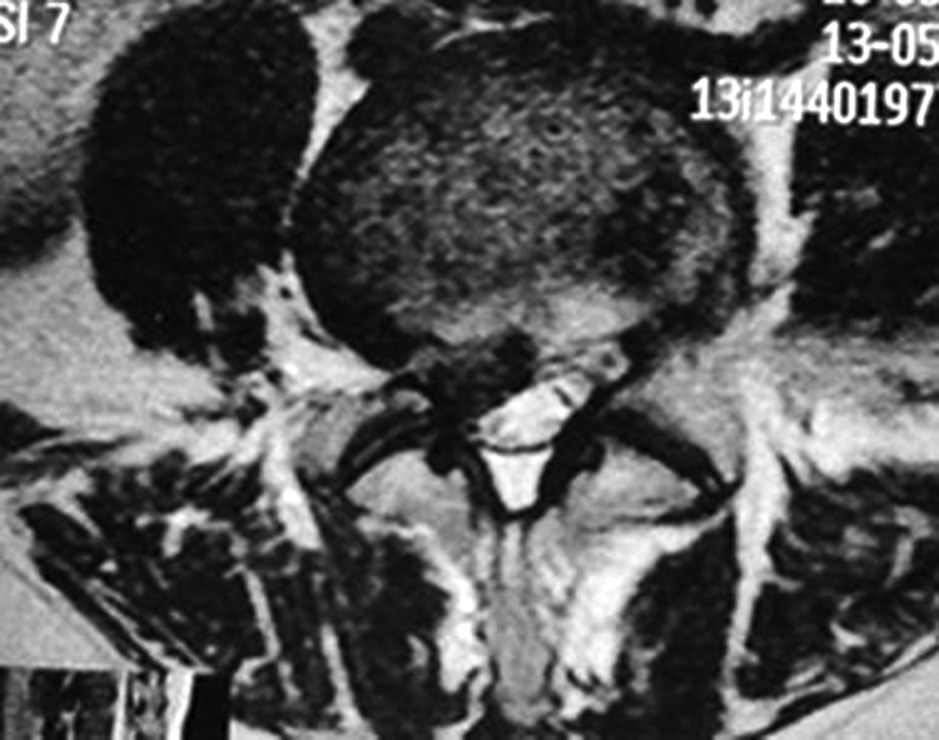

MRI revealed a posterolateral intervertebral disc herniation at L4-L5 with a right-sided foraminal component and severe compression of the right L5 nerve root (Fig. 6).

Fig. 6. MRT scan. Posterolateral herniation of the L4-L5 intervertebral disc with a right foraminal component